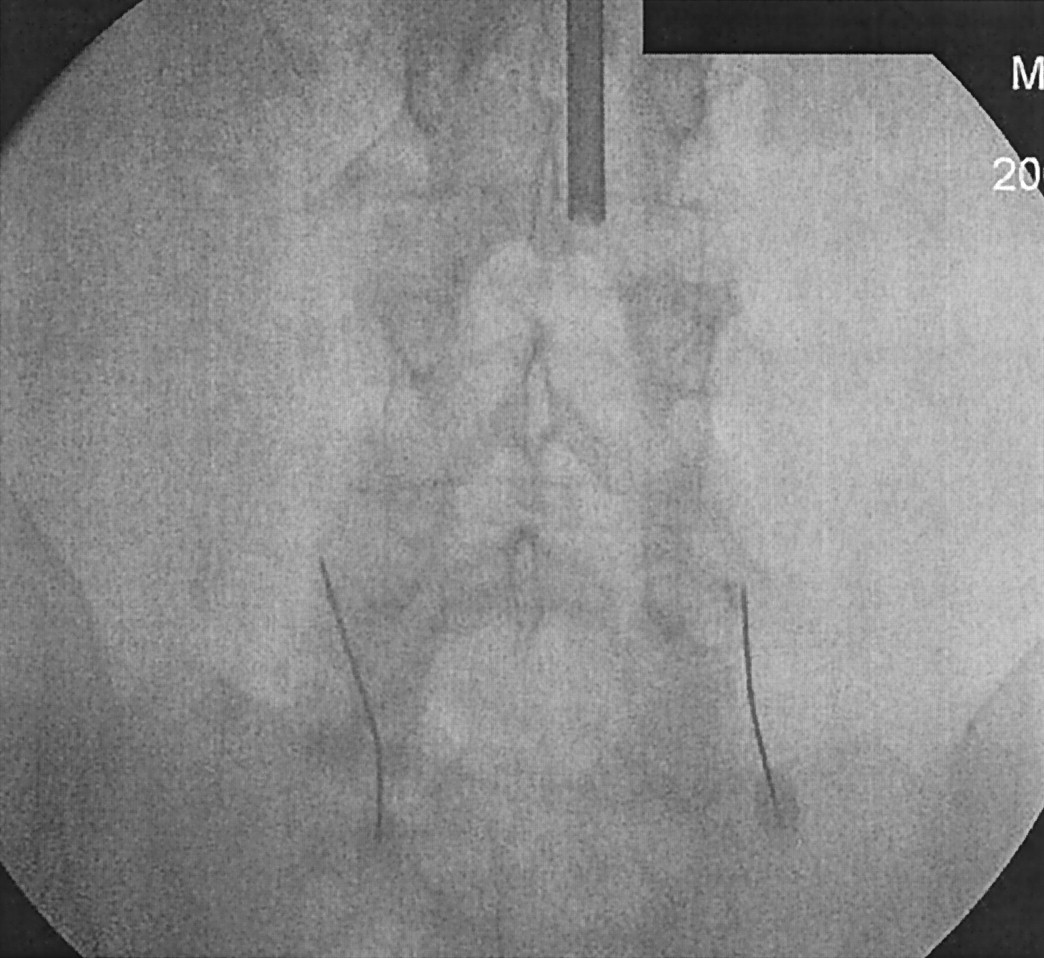

All procedures were performed by the primary author, who is well experienced in both methods. All radiologists and nurses wore protective lead aprons. A spiral CT of the region of interest was done. CT fluoroscopic parameters were chosen (120 kVp, 50 mA). Patients were placed in prone position, and the overlying skin was sterilized. The facet joint was localized using either conventional or CT fluoroscopy. Once localized, a 22-gauge, 3.5-inch needle was directed into the desired facet joint. One needle was used per joint. During CTF, diagnostic accuracy was achieved by ensuring that the position of the tip of the needle was within 5 mm from the superior aspect of the facet of the lumbar spine (Fig 1). For conventional fluoroscopy, the needle tip was placed at the junction between the facet joint and transverse process of the corresponding level (Fig 2). Contrast injections were not used to localize the needles. Once the needles were in place, 1 mL of bupivicane (0.5%) was injected into the joint.

Lumbar facet block at L4–L5 by using conventional fluoroscopy.